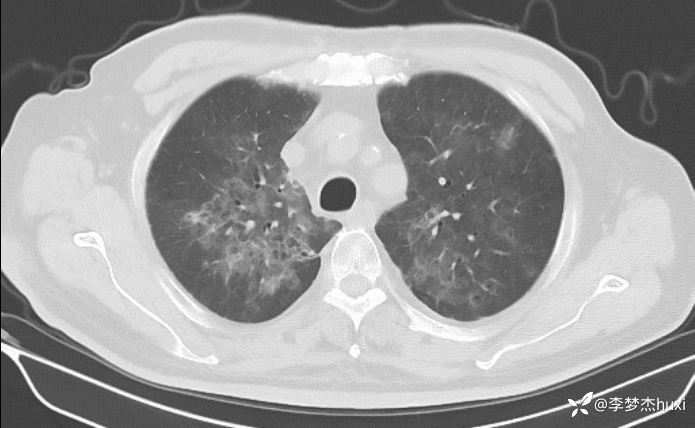

男性74岁,莫西沙星治疗加重的肺炎,可能什么病原菌?

既往史:既往高血压病史 20 余年,最高 180/90mmHg,平素口服降压零号治疗,控制可;糖尿病病史 20 余年,平素应用诺和灵 30R,控制良好;右肺鳞癌病史11月,放疗结束3天,期间放射性食管炎,目前仍吞咽痛;否认冠心病病史;否认“肝炎”、“结核”等传染病史;否认外伤史,否认手术史,无输血史,否认药物、食物过敏史;预防接种史不详,系统回顾无特殊。。

治疗经过:莫西沙星、喜炎平治疗进展

讨论:可能什么病原体?